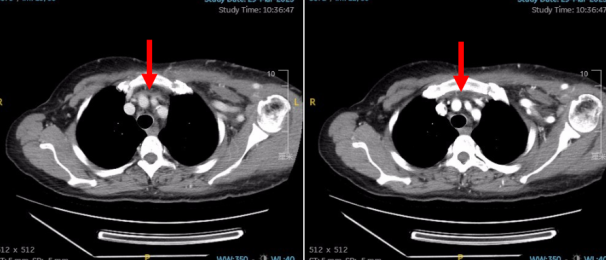

诊断:1、左头臂静脉闭塞,2、慢性肾衰竭尿毒症期,3、高血压。